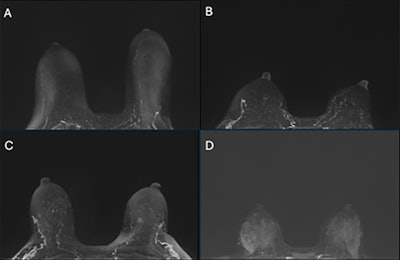

Examples of (A) minimal, (B) mild, (C) moderate, and (D) marked clinical background parenchymal enhancement (BPE) on subtracted postcontrast maximum intensity projection images.RSNA

BPE is evaluated qualitatively by radiologists using BI-RADS categories of minimal, mild, moderate, and marked, but it is subject to interreader variability, according to the authors. Studies have suggested a positive association between increasing ordinal levels of BPE and breast cancer risk, regardless of breast density, they added. Identifying BPE involves the intravenous administration of gadolinium-based contrast agents and an MRI scan to identify areas of vascular enhancement in breast tissue.